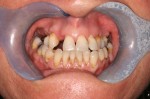

Inflammation of the gums is initially called gingivitis. People who are susceptible to gum disease may progress to get periodontal disease.

Over time, Periodontal disease can damage your ability to bite and lead to tooth loss.

To make sure this doesn't happen, we start treatment promptly to stop the process and maintain your long-term dental health.